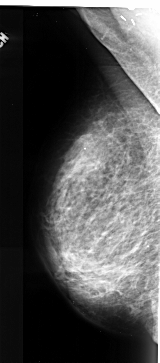

A_1023_1.RIGHT_MLO

RIGHT_CC LINES 5011 PIXELS_PER_LINE 2701 BITS_PER_PIXEL 16 RESOLUTION 42 NON_OVERLAY